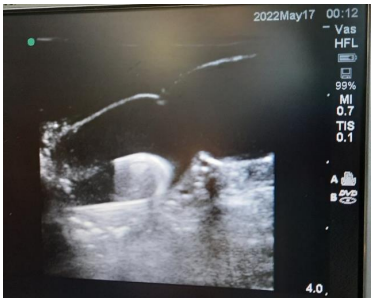

A 25 years old male with hypertension and CKD stage IV presented in the emergency with acute gastroenteritis, acute kidney injury and pulmonary edema due to fluid overload for which urgent hemodialysis with internal jugular vein hemodialysis catheter was planned. Resident Doctor of Internal Medicine performed the catheterization. After completing the catheterization, flow through each port was checked and found normal. One session of hemodialysis was also done which was uneventful. However, when a follow up chest X-ray was done, retained guidewire was identified (Figure 1). Subsequently, an abdominal X-ray was also done (Figure 2). The guidewire extended from hemodialysis catheter lumen to pelvic brim. Intravascular position of missing guidewire was confirmed with USG. An attempt to remove the guidewire by gentle pulling of the hemodialysis catheter failed to retrieve the forgotten guidewire. Therefore, a multi department meeting was conducted. Since endovascular surgery with expertise to retrieve missing guidewire was not available in our centre, consensus was made for surgical retrieval of retained guidewire.

Figure 1: Chest X-ray showing guidewire within hemodialysis catheter.